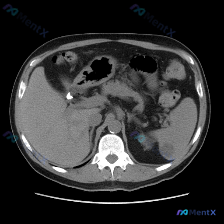

这份是腹部CT软组织窗横断面的平扫影像:

- 脾脏:形态正常,实质密度均匀,未见明确占位性病变;

- 肝脏:轮廓尚可,肝右叶近肝门处可见一类圆形低密度灶,边缘尚清晰,平扫下未见明显钙化或强化特征;

- 胆囊:胆囊颈部或胆囊管区域可见一枚高密度结石影,胆囊壁无明显增厚;

- 其余胰腺、左肾、肾上腺、腹膜后淋巴结、血管、腹腔肠道等均未见明确异常,无腹水。